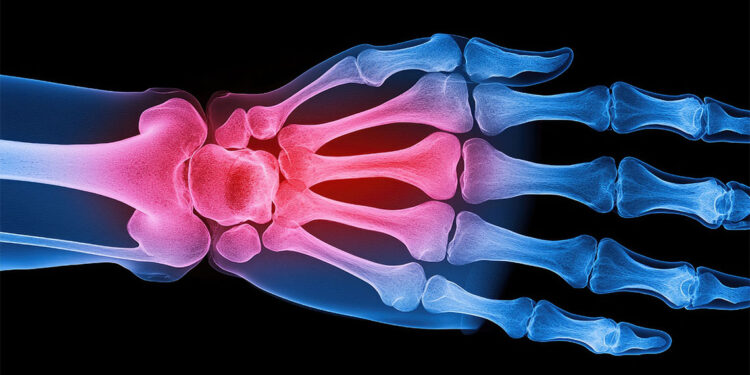

Uzm. Dr. Tunçay, kemik erimesi gelişen kişilerde bel ve sırt ağrısı, boyda kısalma, omurgada kırık; sırtta kamburlaşma, omuzlarda yuvarlaklaşma; el bileğinde kırık, kaburga kırıkları ve kalça kemiğinde kırık olabileceğine dikkat çekti.

OMURGA, EL BİLEĞİ VE KALÇADA DAHA SIK

Osteoporozda kırıkların tüm kemiklerde olabilmekle birlikte sıklıkla omurga, el bileği ve kalça kemiklerinde görüldüğünün altını çizen Uzm. Dr. Tunçay, şu bilgileri paylaştı: